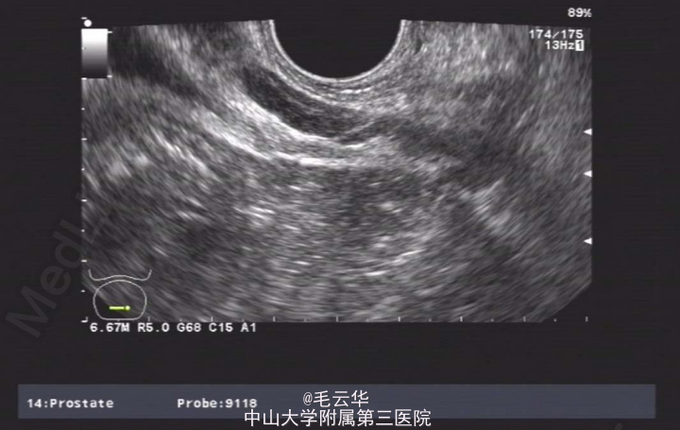

双肾区无红肿、隆起,无叩痛,双侧肋脊点、肋腰点无压痛。腹平软,双侧上中输尿管点无压痛,膀胱区无压痛。双侧腹股沟区未触及肿物,尿道外口未见异常,阴囊无水肿,双睾丸可触及,肛周皮肤无红肿。盆腔MR提示:双侧精囊腺体积缩小(未见片)。彩超提示:右侧输精管、精囊缺如可能;双侧睾丸偏大,附睾小管扩张;前列腺囊肿。精液常规提示精液量少,离心后无精子。

入院诊断:无精症查因。 入院完善术前相关检查,射精管切开+输精管探查术。麻醉成功后,取截石位,常规消毒铺巾,连接好4.5/6.5F输尿管硬镜和监视系统。经尿道进镜入膀胱,见双侧输尿管开口裂隙状,膀胱内未见异常。尿道未见明显异常,精阜稍隆起。镜下未找到双侧射精管开口,硬膜外导管引导进镜入前列腺小囊,见囊腔狭小,囊壁炎性增厚,囊内未见射精管开口,考虑射精管口梗阻,遂换用电切镜,切除部分精阜,切开双侧射精管口,再用硬膜外导管引导输尿管硬镜入射精管,进入困难,结合病史及影像学检查,提示射精管发育不良并梗阻。作双侧阴囊切口,逐层切开,游离出睾丸和精索,探查双侧输精管,见左侧输精管呈纤维条索状,未见管腔结构,右侧未见输精管,考虑为先天缺如,遂行双侧睾丸活检,术野予以止血,逐层缝合切口,术毕。手术过程顺利,麻醉效果满意,术中无出血,术后安返病房。